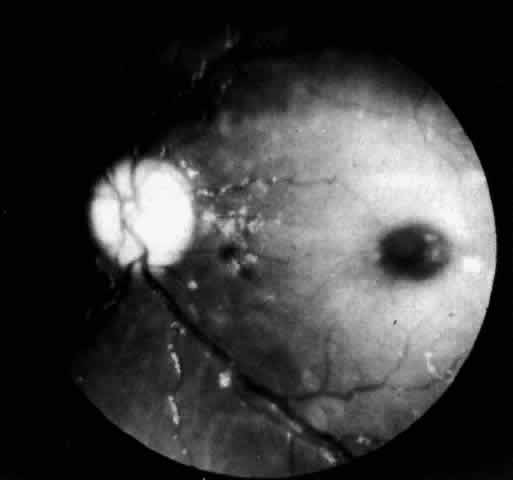

In three patients with type III subacute juvenile neuronopathic Gaucher's disease however, the retina showed a unique retinopathy. The findings in Cogan's case 1 are described: “Both fundi showed discrete white spots randomly distributed in the posterior fundus, especially along the inferior vascular arcades (Fig. 8). The spots varied in diameter from just visible to approximately 0.1 mm and were situated in the superficial retina or on the surface of the retina. Several covered the retinal vessels. The disc and retinal vessels were normal.” The child, an 11-year-old boy, had normal acuity and a full field of vision by confrontation. He had presented at age 3 years with splenomegaly.

Fig. 8. Fundus of a patient with type III subacute juvenile neuronopathic Gaucher"s disease showing discrete white spots in or on the retina along the inferior vascular arcades. At least one spot overlies a vein. The optic disc and retinal vessels were normal. (Cogan DG, Chu FC, Gittinger J, Tyshsen L: Fundal abnormalities of Gaucher"s disease. Arch Ophthalmol 98:2202, 1980. Copyright © 1980, American Medical Association)

Normal vision and similar retinal abnormalities were observed in a mildly mentally retarded 18-year-old woman (case 2) presenting with splenomegaly at age 1 year and in a 6½-year-old boy (case 3) noted to have hepatosplenomegaly in the first year of life. The patients in cases 1 and 3 had conspicuous supranuclear defects of eye movement.

An electron microscopic study of Gaucher's cells in the eye in type III juvenile neuronopathic disease is reported from Japan by Ueno and associates87,88 who noted white spots in an arcuate pattern in the fundi of an 8-year-old Japanese boy. At autopsy the retinal spots corresponded to polymorphonuclear giant cells within and on the surface of the retina. These cells were large and stained positively for glycolipid and acid phosphatase.